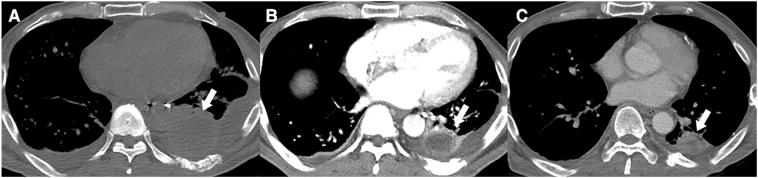

Traumatic pulmonary giant hematoma, resulting from blunt trauma, is a relatively rare event. Here, we report the rare case of a patient with a giant traumatic pulmonary hematoma that was associated with blunt trauma. A 50-year-old man was admitted to our medical center after a fall from a height of 5 m. He was diagnosed with pulmonary contusion, and tests showed a huge pulmonary hematoma of approximately 8.2 × 5.3 × 13.2 cm in the left lung field along with other significant injuries. Treatment comprised of aggressive coagulation management, broad-spectrum antibiotics, and pulmonary hygiene. The patient's symptoms gradually improved and magnetic resonance scan revealed that he did not develop an abscess formation. No complications were seen at the 6 months follow-up visit. If the above mentioned measures would have failed to control the bleeding or secondary infection, then emergency surgery would have been warranted. Awareness of this kind of injury and efforts to reduce infection are important to guide the giant traumatic pulmonary hematoma to the benign course.

创伤性肺巨大血肿由钝性创伤引起,是一种相对罕见的情况。在此,我们报告一例与钝性创伤相关的创伤性肺巨大血肿的罕见病例。一名50岁男性从5米高处坠落后来到我们的医疗中心。他被诊断为肺挫伤,检查显示左肺野有一个巨大的肺血肿,大小约为8.2×5.3×13.2厘米,同时伴有其他严重损伤。治疗包括积极的凝血管理、广谱抗生素和肺部护理。患者的症状逐渐改善,磁共振扫描显示他没有形成脓肿。在6个月的随访中未发现并发症。如果上述措施未能控制出血或继发感染,则有必要进行急诊手术。认识到这种损伤并努力减少感染对于引导创伤性肺巨大血肿走向良性病程很重要。